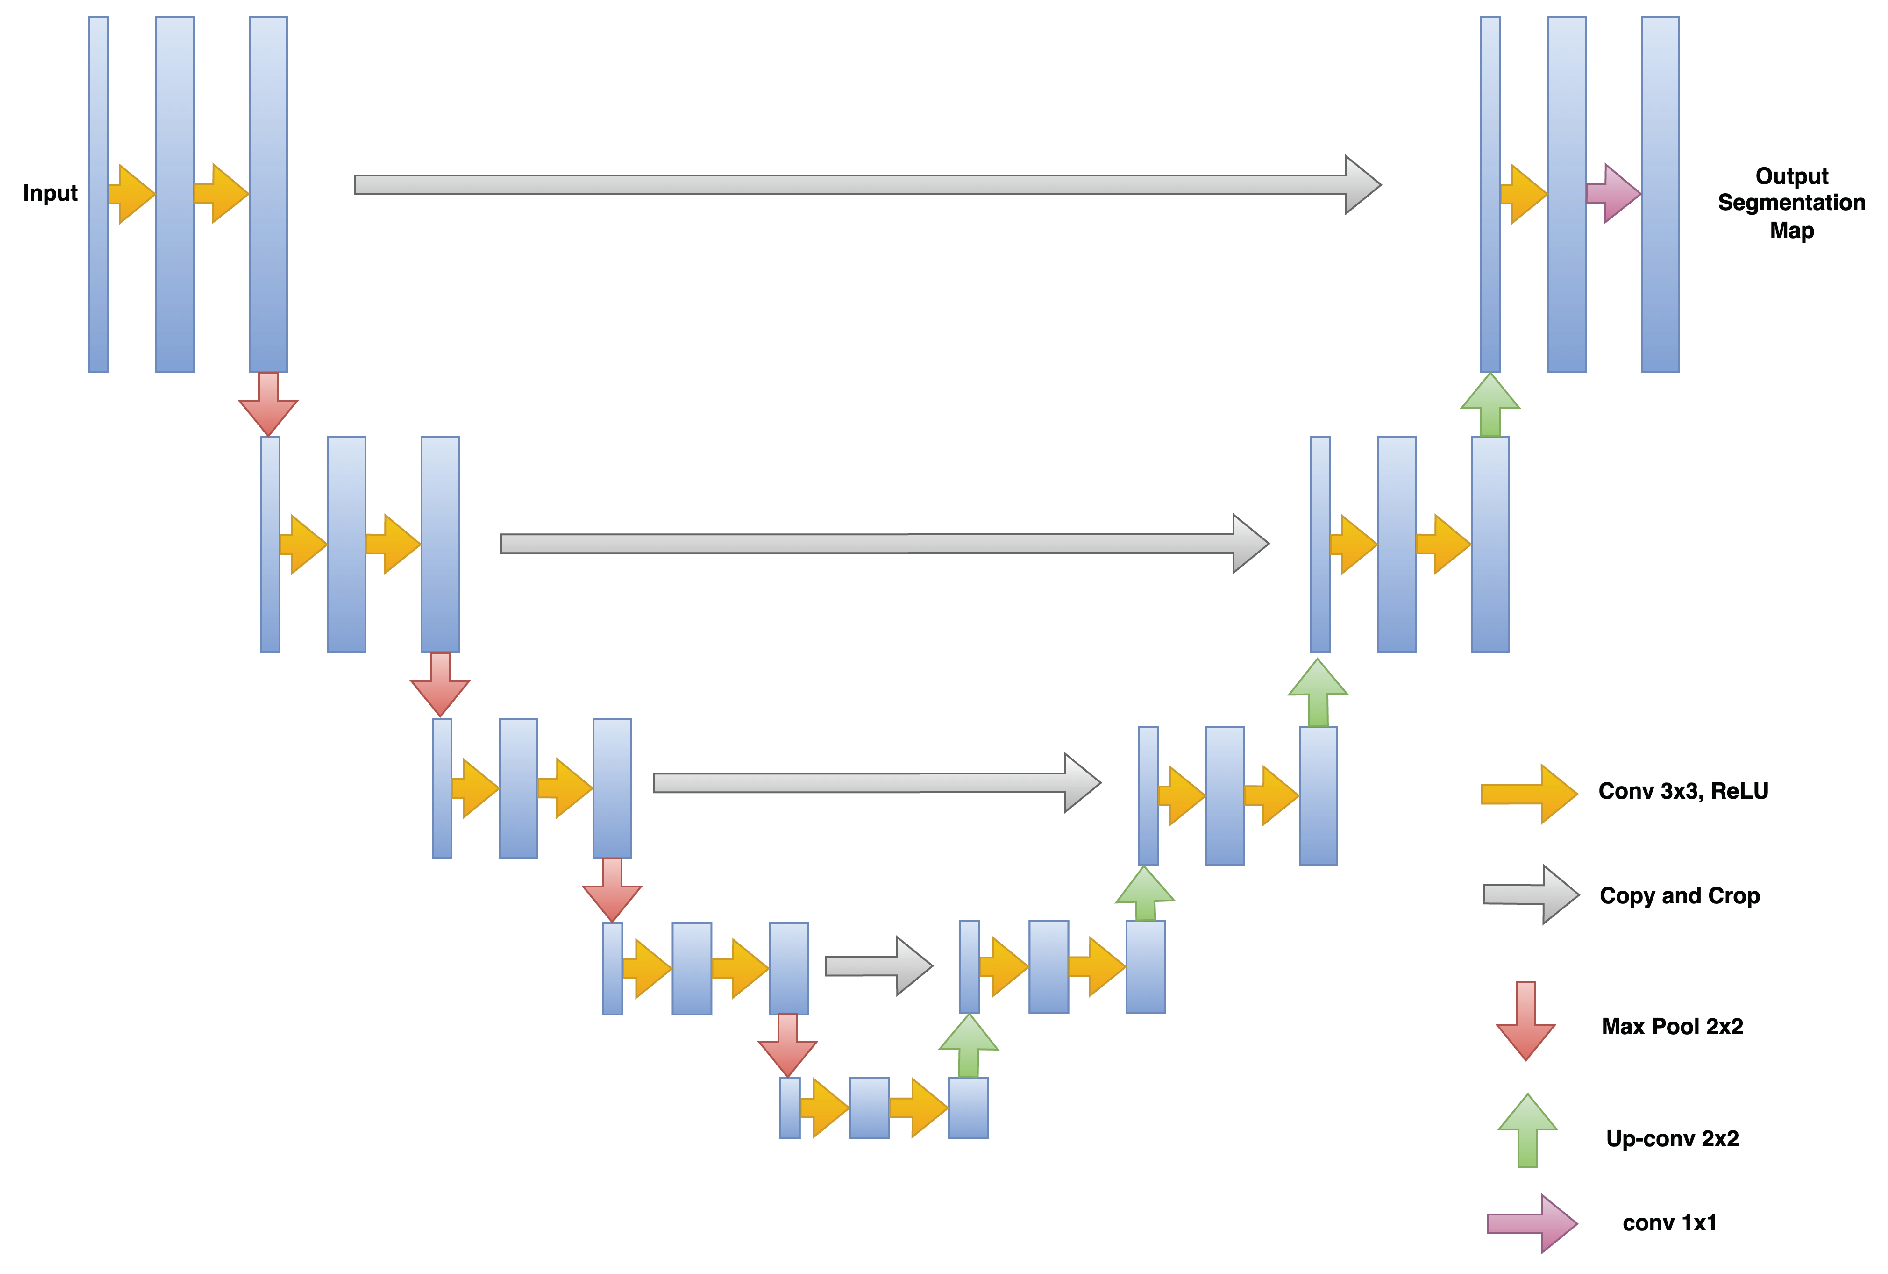

3.1.1. Disorganization of Retinal Inner Layers (DRIL)

3.1.2. Hyperreflective Focii (HRF)

3.1.3. Cystoid Space